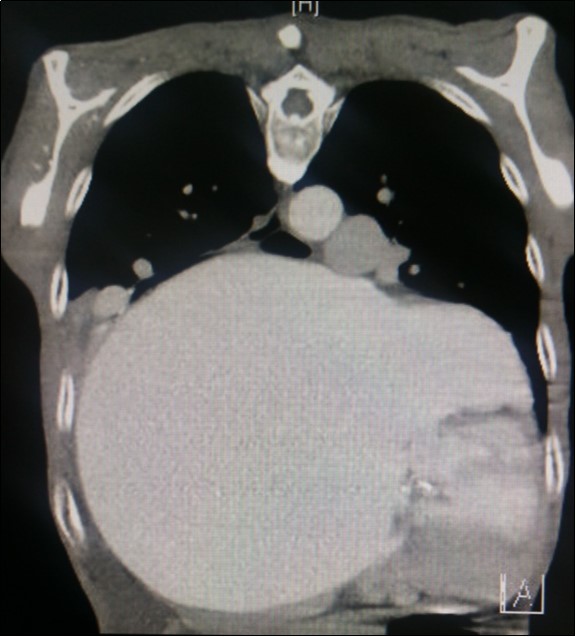

A dramatically dilated left atrium was seen on a TTE (see Figure 2a, Figure 2b, Figure 2c, and Figure 2d). Severe mitral stenosis with associated regurgitation was evident, with a mean gradient across the valve of 11mmHg and a hyperdynamic left ventricle. The left atrial volume measured by Simpson’s biplane method (see Figure 2c) was 2108mL, or 1548.5 ml/m2, based on height 1.55 metres and weight 44 Kg. Normal left atrial volume in a woman is 16 - 34 ml/m21. The computed tomography scan (CT) chest AP view (see Figure 3) is also shown.

Figure 3.Computed tomography scan (CT) chest AP view, showing the extent of the left atrium filling the left and right hemithoraces.